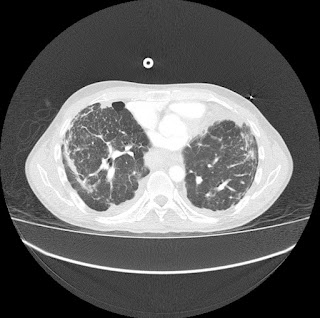

Escanografía